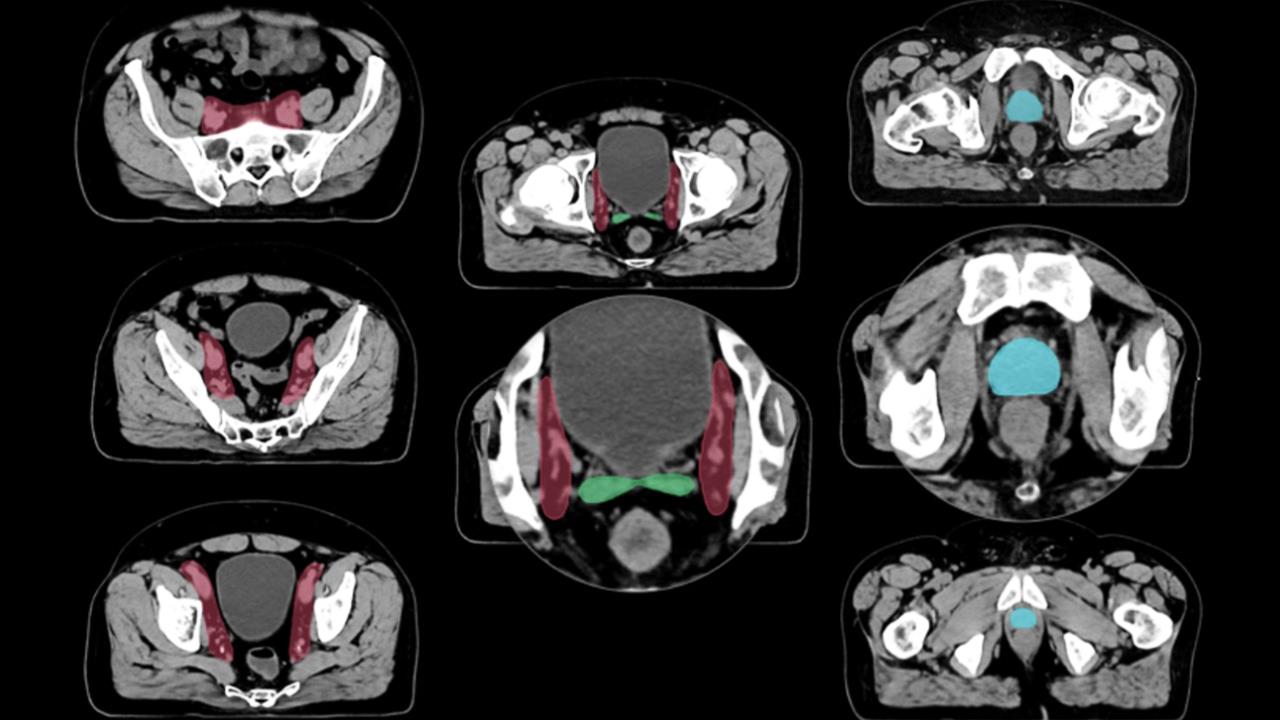

Το Ακτινοθεραπευτικό Ογκολογικό τμήμα του Α.Ν.Θ "Θεαγενείου", πάντα πρωτοπόρο στη χρήση τεχνολογίας αιχμής και εφαρμογής τεχνικών υψηλής τεχνολογίας, μετά από ένα εξάμηνο έρευνας και δοκιμαστικής χρήσης διαφόρων παρόμοιων εφαρμογών εγκατέστησε - μέσω διαγωνισμού το λογισμικό Limbus AI, πρώτο από όλα τα ακτινοθεραπευτικά κέντρα της Β. Ελλάδος - λογισμικό τεχνητής νοημοσύνης που βελτιώνει το work flow της ακτινοθεραπείας με αποτέλεσμα τη βελτίωση της ποιότητας της ασφάλειας και της έγκαιρης παροχής ακτινοθεραπείας στους ασθενείς.

Η ακρίβεια και η ποιότητα του λογισμικού της τεχνητής νοημοσύνης έχει αποδειχθεί σε πολυάριθμες κλινικές μελέτες και έχει εγκριθεί από διεθνείς επιστημονικές εταιρείες της ακτινοθεραπείας (Astro - Estro). Η Estro έχει σχεδιάσει δομές στο μαστό, στην πύελο και στο head and neck και όλα τα επίπεδα των λεμφαδενικών περιοχών αυτών των δομών τα οποία εμπεριέχονται στο "Limbus AI".

Το συγκεκριμένο εργαλείο τεχνητής νοημοσύνης που έχει πλέον εδραιωθεί σε μεγάλα κέντρα ακτινοθεραπείας παγκοσμίως, προσφέρει ταχύτερους χρόνους ακτινοθεραπείας, κάνει πιο εφικτή την τεχνική της adaptive ακτινοθεραπείας και του replanning (επανασχεδιασμού).